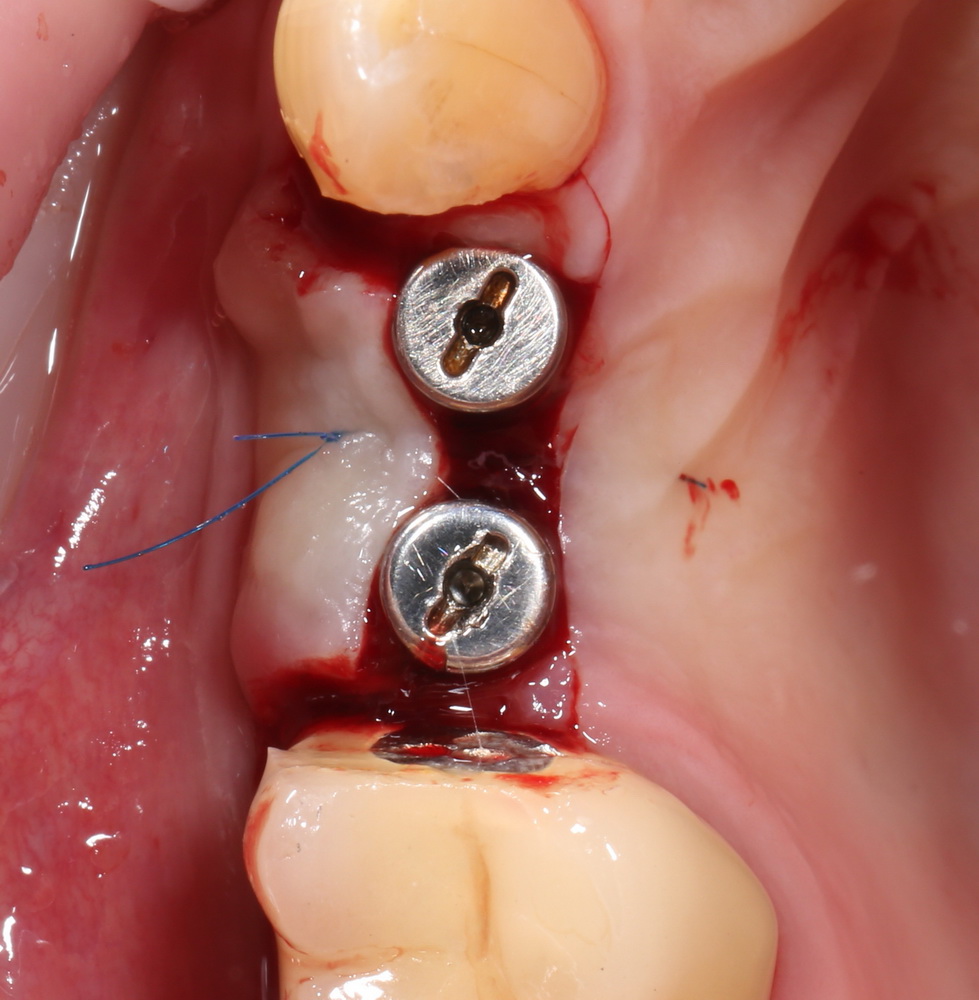

Делаем разрез, смотрим, что там с имплантами. А с ними всё в порядке:

Как и с окружающей их костной тканью:

Обратите внимание, до какого уровня имплантат находится в костной ткани. До полированной фаски — и это правильное расположение и глубина погружения XiVE. У разных имплантационных систем они могут отличаться — см. инструкцию.

Мы ставим формирователи десны: